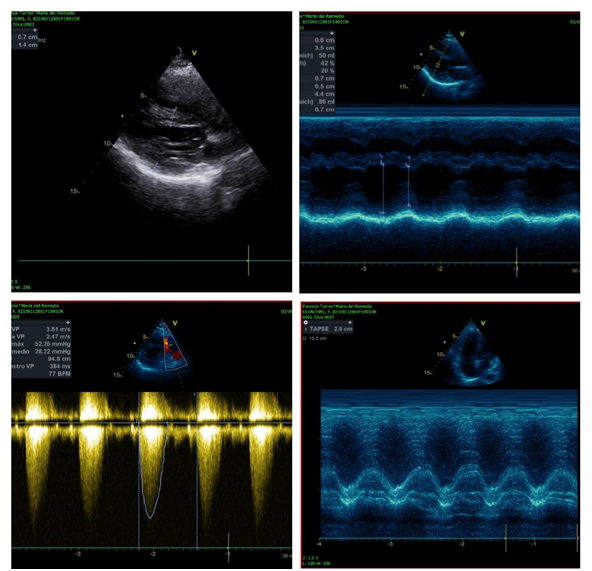

Acid-base balance without apparent complications ph: 7.41, pO2 43, pCO2 31, HCO3: 19, laboratories (Table 1), Tele chest (figure 2), electrocardiogram (figure 3), echocardiogram (figure 4). The abdominal route is interrupted under epidural anesthesia. Pregnancy with the following findings obtaining on 04-03-2020 at 11:29 hrs. R.N. female weight 2120g, size 44cm. APGAR 5/7, Capurro 34 SDG. After a surgical event, she admits to the ICU as multidisciplinary management; oxygen supplementation starts, and the latter prophylactic low-molecular-weight heparin, after four days of ICU treatment with favorable evolution, is admitted to the gynecology floor to begin cardiac rehabilitation and continuous monitoring, thus progressing correct deciding discharge from the service.

Figure 4 Echocardiogram 03-06-2020. Non-dilated non-hypertrophic left ventricle, without intracavitary thrombi, without alterations in contractility, with a moderately depressed LVEF of 42%, due to teicholz, moderate diastolic dysfunction due to a type 2 pattern. Undilated right ventricle hypertrophy, without intracavitary thrombi, preserved systolic function, with TAPSE of 20 mm, ventricular septal defect with an aortic thrust of 30%, in fundibular pulmonary stenosis with a maximum gradient of 52 mmHg, medium 28mmHg.